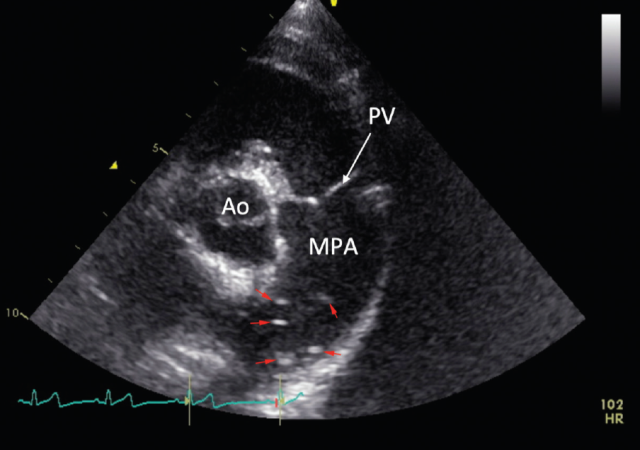

Thoracic radiographs revealed enlargement of the pulmonary arteries, mild to moderate right ventricular enlargement and a moderate diffuse, unstructured interstitial pattern with patchy alveolar areas within the right cranial and middle lung lobes (see Figures 1 and 2). Echocardiography revealed right atrial enlargement with bulging of the interatrial septum to the left, mild subjective enlargement of the right ventricle and mild to moderate central pulmonic regurgitation with a mildly elevated velocity (2.8m/s; reference value <2.2m/s). The pulmonary artery was mildly enlarged and contained multiple mobile, tortuous linear hyperechoic structures, likely to reflect the presence of adult worms (see Figure 3). The laboratory test results in combination with the imaging findings were consistent with a diagnosis of canine dirofilariasis.